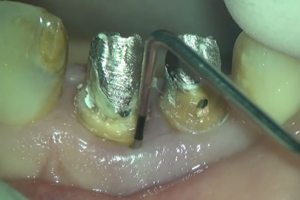

精密根管治療(歯の根の治療)

歯の根の治療(根管治療)は、家でいえば「基礎工事」にあたる非常に重要な工程です。

しかし、根管は非常に細く、複雑に枝分かれしており、肉眼ではその中を直接見ることは不可能です。

マイクロスコープを使用することで、根管の入り口や、隠れた管、さらには過去の治療で取り残された充填剤などを視認しながら除去できます。

精密な清掃

感染した組織(細菌)をできる限り取り除き、再発のリスクを軽減することを目指します。